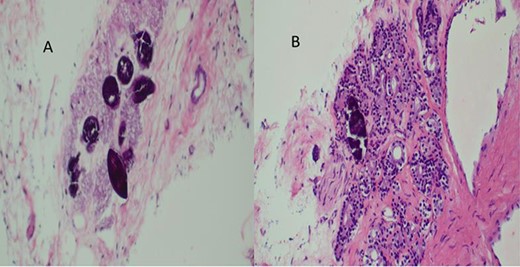

A total of six core biopsies were taken from multiple sites of the prostate. Histopathological examination confirmed the presence of invasive prostatic adenocarcinoma Gleason score 7 (4 + 3) and Schistosoma hematobium eggs (Fig. 5). The patient received a single dose of Praziquantel (40 mg/kg) for the treatment of Schistosomiasis. The patient was referred to oncology department for further management; unfortunately, he got lost to follow-up.

(A) Histopathology of prostatic trucut core biopsy showing infiltrating adenocarcinoma and Schistosoma ova, H&E ×4, ×10 magnification. (B) Prostatic adenocarcinoma and Schistosoma ova, ×40 magnification.